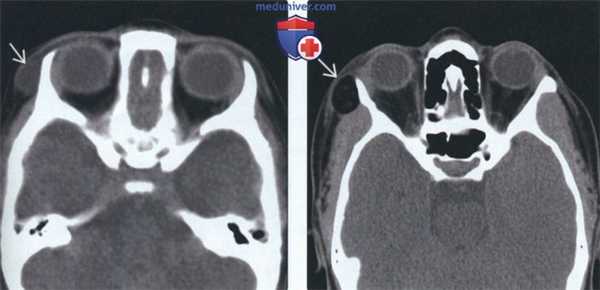

2. КТ дермоида и эпидермоида полости рта:

• КТ без КУ:

о Гиподенсное кистозное образование с четкими контурами:

- Эпидермоид: содержит материал жидкостной плотности без признаков усложнения структуры

- Дермоид: материал жировой плотности, жидкость смешанной плотности, кальцинаты (<50%):

Если содержит жидкость без признаков усложнения структуры, неотличим от эпидермоида

о Типичные фестончатые дефекты или ремоделирование кости

• КТ с КУ:

о Стенка кисты может быть неразличима

о Иногда наблюдается едва заметное контрастирование стенки в виде «ободка»

(Слева) На аксиальной КТ без КУ у четырехлетней девочки снаружи от латеральной стенки правой глазницы визуализируется ги поденсное объемное образование с четкими контурами без включений жира или кальцинатов; дифференциальная диагностика проводится между дермоидной и эпидермоидной кистой. При патоморфологическом иссле довании обнаружились придатки кожи, что позволило сделать заключение о дермоидной кисте.

(Справа) На аксиальной КТ без КУ у ребенка с длительной существующим пальпируемым объемным периорбитальным образованием визуализируется хорошо отграниченный дермоид, содержащий жир, сглаживающий наружную стенку глазницы.